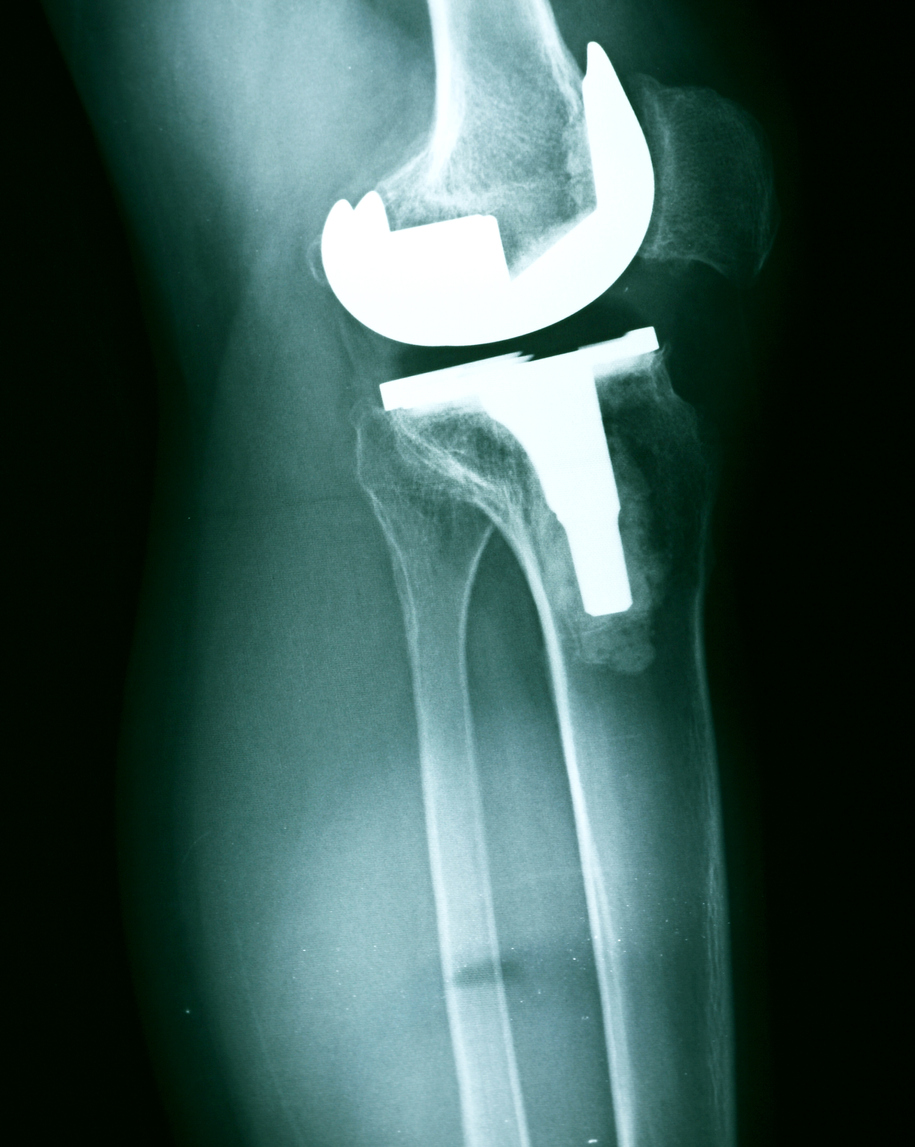

Myths of Knee Replacement Surgery

There are approximately 700,000 knee replacements performed each year in the United States. It is one of the most frequently performed joint replacement procedures. However, there are a lot of misconceptions about knee replacement surgery. Let’s take a few minutes to bust some of these myths!

“Knee replacement is only for elderly people. ”

This is a big myth! While a lot of older people get knee replacement procedures done, it is not a procedure exclusive to their age group. People of all ages can get knee replacement surgery when its necessary (i.e. the knee joint is damaged beyond repair). This is common for younger individuals with regenerative diseases or after an accident damages the knee joint very badly.

“Knee replacement will limit what I can do with my life.”

Some people believe that after a knee replacement, they cannot be as active as they used to be. It’s actually quite the opposite! Knee pain can keep you from doing the things you love such as exercising, hiking, running, and simply enjoying life the way you want to. After a knee replacement, your knee will function the way it is meant to. This restoration of function will give you the ability to do all the things you want that you previously couldn’t do because of a bad knee joint.

“I will be forced into bed rest for months after my surgery. ”

Not true! You will begin using your knee and getting active as quickly as possible following your surgery. Immediately following your procedure, your surgeon will recommend you start moving – slowly and gradually. In the beginning, you will use crutches and walkers to assist you as you walk and get the new knee moving. After just a few weeks of healing, you will begin physical therapy to regain strength and functionality back in the knee.

“Once I get a prosthetic knee, my days of playing sports are over.”

This is definitely not true. You will actually be able to play more sports than you did before! A knee replacement surgery is done when the existing knee joint is beyond repair and is causing substantial difficulty when used. When you get a knee replacement surgery, your knee will become more functional and less painful than before. This will allow you to do things you couldn’t before – like playing sports.

Orthopedic Care and Knee Replacement Surgery in North Dakota

If you have knee problems and want to explore whether knee replacement surgery is right for you, contact the experts at The Bone & Joint Center. We have substantial experience treating all types of orthopedic conditions such as knee pain and would love to serve you at one of our 18 locations throughout North Dakota. To make an appointment, call (800) 424-2663 or request an appointment online.